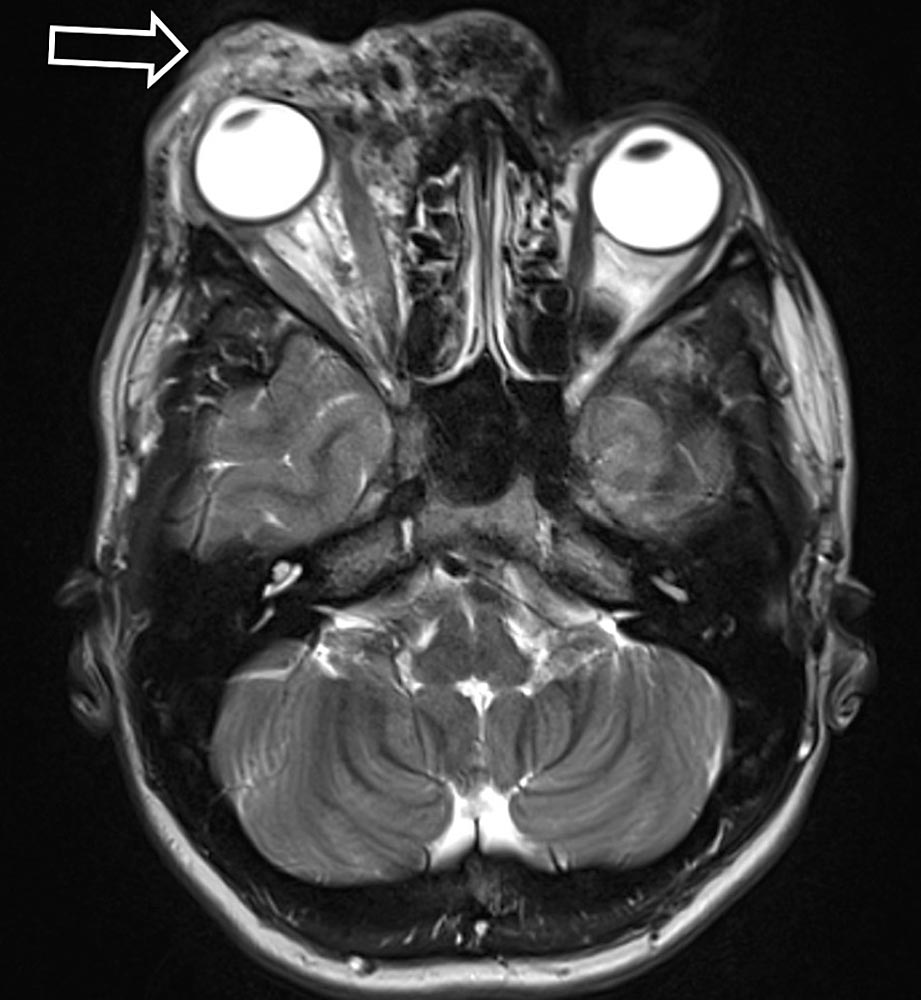

Owing to the presence of shunts, this swelling may be associated with pulsation and increasing, spreading warmth. As a result of the increased volume and pressure load in the venous system, symptoms of chronic venous insufficiency may ensue. Both venous insufficiency and reduced arterial blood flow peripheral to the nidus can lead to a diffuse spread of pain. Compression or invasion of the surrounding tissue, caused by shunts and dilated vessels, can additionally cause functional and movement restrictions (e.g., muscle contractures, joint or bone involvement).

• Destruction and functional limitation because of compression, displacement and invasion by the AVM